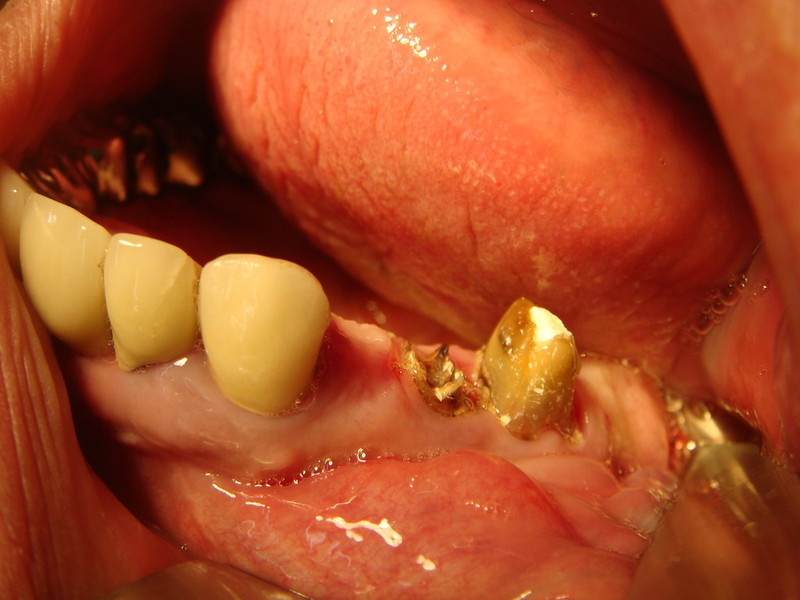

rigenerazione grave difetto parodontale a carico del 46